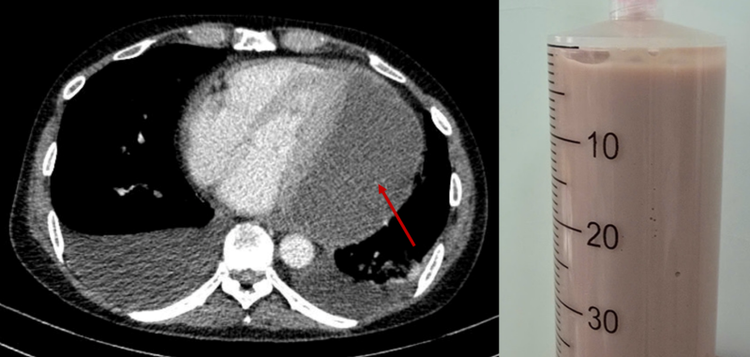

Tuy nhiên, nhờ kinh nghiệm chuyên môn và sự hỗ trợ của thiết bị siêu âm hiện đại tại giường bệnh, các bác sĩ đã hút thành công 500ml mủ đặc, giảm nhanh áp lực lên tim. Kết quả xét nghiệm cho thấy đây là một ca viêm mủ màng ngoài tim nặng, không do vi khuẩn lao hay ký sinh trùng.

Lớp dịch mủ chèn ép tim và dịch mủ đặc rút ra được qua chọc dịch màng ngoài tim - Ảnh BVCC